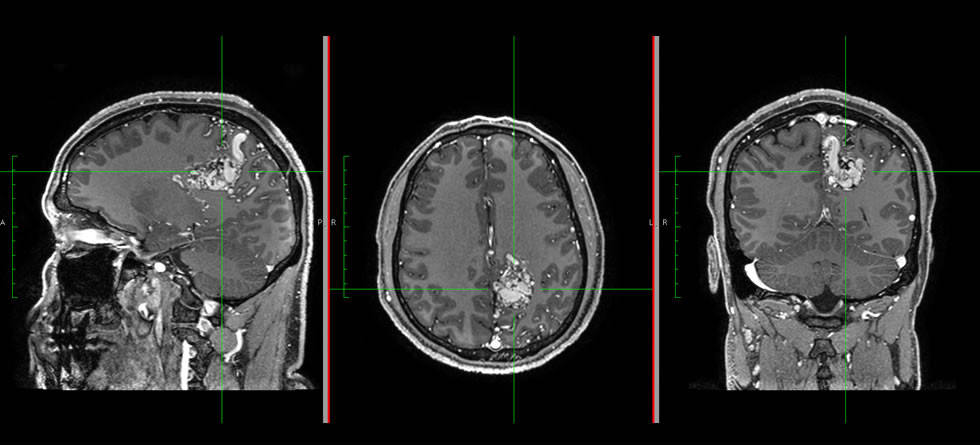

Interpretación de Estudios de Resonancia Magnética

La lectura de estudios de Resonancia Magnética es realizada por profesionales sub-especializados que garantizan alta calidad en su interpretación, t...

Leer más -